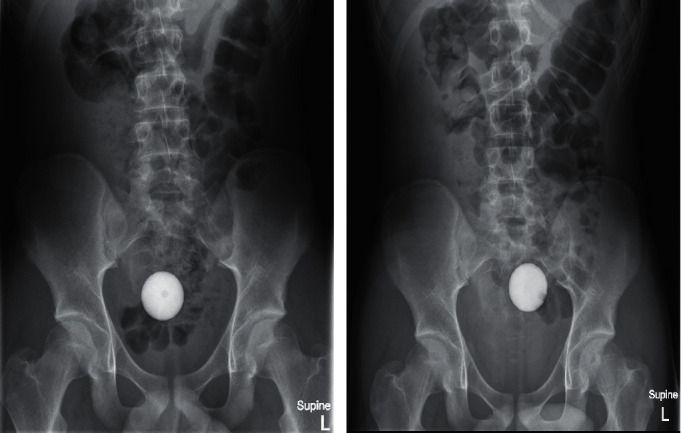

Bola golf tersangkut di usus Foto: Case Reports in Surgery |

Seorang remaja berusia 14 tahun di Australia nekat memasukkan bola golf ke dalam duburnya. Setelah diperiksa melalui x-ray, bola golf tersebut menuju ke kolon sigmoidnya, bagian terakhir dari usus besar yang terhubung ke rektum (dubur).

Kasus yang tercatat dalam Case Reports in Surgery melaporkan berbagai upaya dokter untuk mengeluarkan bola golf dari tubuh remaja tersebut. Bola golf tersebut bahkan masih berada di tempat semula setelah 24 jam.

Keluarga anak laki-laki itu dilaporkan tidak tertarik pada dokter yang melakukan lebih banyak upaya operasi, sehingga spesialis medis memberikan satu liter obat pencahar. Tiga jam kemudian, dokter berhasil mengeluarkan bola golf tersebut tanpa menyebabkan cedera pada usus.

"Bola golf menghadirkan tantangan teknis yang unik saat mencoba mengeluarkannya dari usus besar karena sifat mekanisnya," tulis penulis laporan tersebut.

"Ini termasuk ukurannya yang besar, bentuk bulat, tidak dapat dimampatkan, dan adanya tekstur, yang mencegah segel hisap," lanjut laporan tersebut.